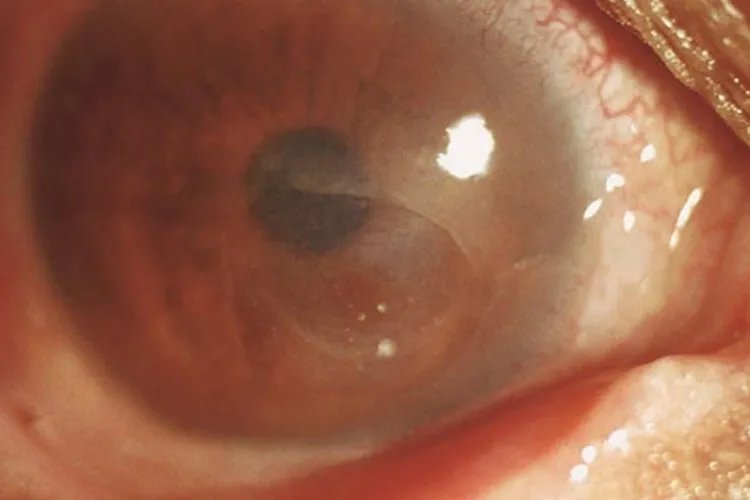

的有关信息介绍如下:概述角膜炎初期症状多见于角膜上皮病变,常为角膜溃疡、水疱、浑浊等。临床上可将角膜炎分为感染性角膜炎和非感染性角膜炎。角膜炎病因较多,与外界或内源性致病因素侵袭角膜组织相关。症状感染性结膜炎细菌性角膜炎本病起病急骤,病变早期表现为角膜上皮溃疡,溃疡下有边界模糊、致密的浸润灶,周围组织水肿。

真菌性角膜炎起病缓慢,亚急性经过,临床表现早期症状较轻,发展缓慢,为角膜浅层溃疡。单纯疱疹病毒性角膜炎单纯疱疹病毒性角膜炎中上皮型结膜炎初期病变显著。上皮型角膜炎感染初期角膜上皮层可见灰白色、近乎透明、稍隆起的针尖样水疱,点状或排列成行或聚集成簇,一般仅持续数小时至十余小时,因此常被忽略

棘阿米巴角膜炎感染初期表现为上皮混浊、微囊样水肿或假树枝状,上皮可完整,少数患者可出现特征性放射状角膜神经炎。